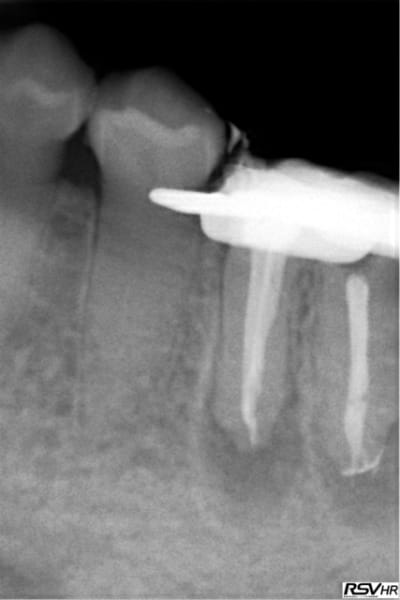

Tu peux me faire un CBCT de 35 ? Il semble y avoir un 4ième bien que le tt endo soit correct.

Je viens de faire une bio sur 45 (pulpite). Et je crois que j'ai ma petite idée sur la cause du 4 ième de 35. -)

Capture d e cran 2016 02 10 10.04 - Eugenol

Capture d e cran 2016 02 10 10.05 - Eugenol